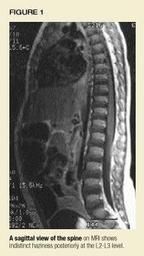

The MRI provides the long-awaited key to the diagnosis. An abnormal increasedsignal is found in the thecal space in the lumbar spine, suggesting a spinalepidural abscess or an infected hematoma (Figure 1). Hyperdense signalsare found at the level of the L2-L3 facets on the right and the surroundingsoft tissues (Figure 2).

MRI is the preferred imaging technique to uncover the possibility ofa spinal epidural abscess. CT scans with contrast may be helpful, but bonescans and plain radiographs are usually negative unless there is an associatedosteomyelitis.2 The management of this abscess in children isimmediate surgical drainage with laminectomy, and parenteral antibiotics.